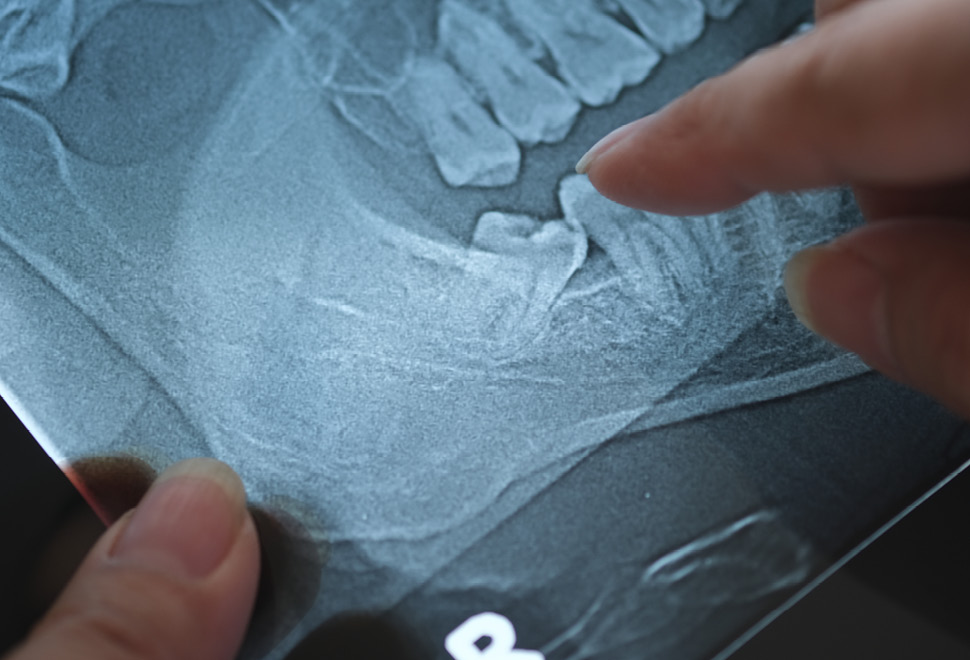

De behandeling start met een consultatie waarbij we de positie van de wijsheidstanden beoordelen via klinisch onderzoek en een panoramische röntgenfoto (OPG). Zo krijgen we inzicht in hun ligging, wortelvorm en de relatie tot omliggende structuren zoals zenuwen en sinussen.